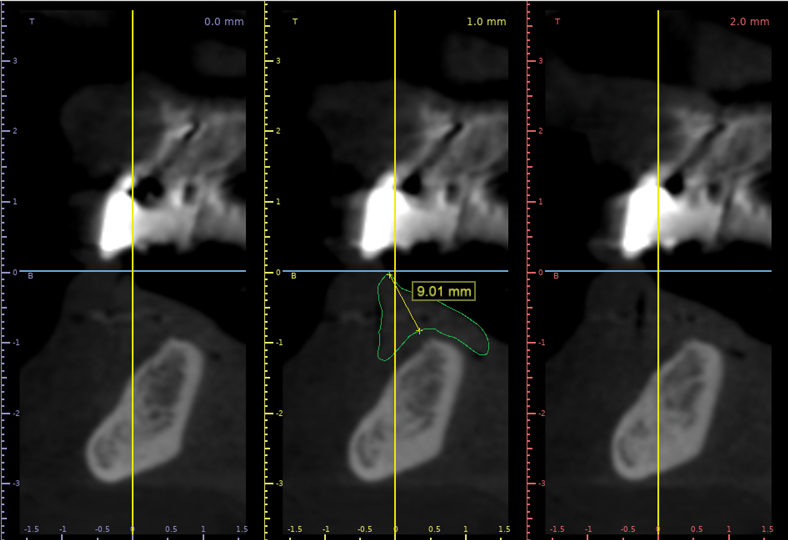

Radiographic measurements may be taken after capture of a CBCT image of both the patient and prosthesis using a dual-scan protocol and imaging software. Measurements are taken from the intaglio surface of the denture to the occlusal surface utilizing fiduciary markers to align the prosthesis (Figure 4 and Figure 5).

Fig 4. Radiographic measurements to establish the amount of prosthetic space available; these measurements aid in planning prosthetic space and implant placement. Fig 4 demonstrates a method to measure the apico-coronal dimensions of the restorative prosthesis. Fig 5 allows for assessment of the implant position planned based on radiographic bone volume and prosthesis positions.

Figure 4

Fig 5. Radiographic measurements to establish the amount of prosthetic space available; these measurements aid in planning prosthetic space and implant placement. Fig 4 demonstrates a method to measure the apico-coronal dimensions of the restorative prosthesis. Fig 5 allows for assessment of the implant position planned based on radiographic bone volume and prosthesis positions.

Figure 5